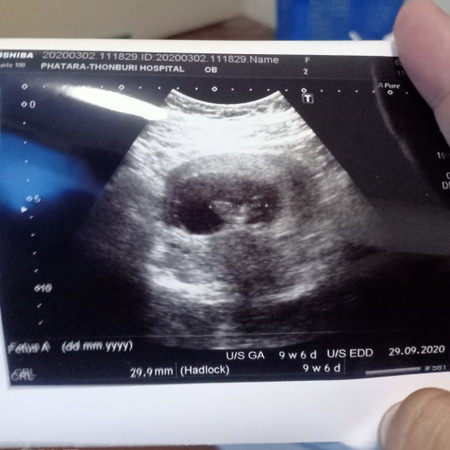

อัพเดทภาอันต้าซาวด์หน่อยค่ะ

ของแม่ 10 Week หัวใจน้องก้เต้นดีมาก ตอน 5 Week หมอบอกหัวใจน้องไม่เต้นแต่พอ10week เปลี่ยนลองไปหาหมอคนใหม่น้องกลับปกติ ถ้ามีใครเป็นเควสแบบแม่แนะนำให้รอก่อนน่ะค่ะ อย่าพึ่งทำอะไรกับน้อง ตัวแม่เองก็คิดว่าจะเสียน้องไปแล้ว แต่สุดท้ายน้องก้รอดด ?✌️